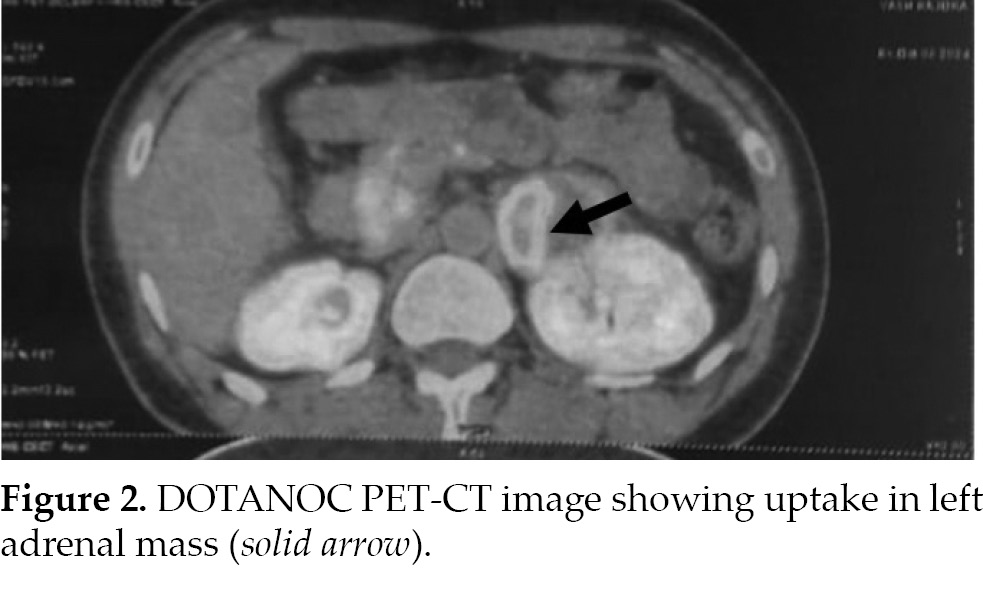

elevated at 3,910 ng/L (normal range: 7.90-88.7 ng/L). A DOTANOC-PET/CT scan indicated increased uptake in the left adrenal mass with no abnormal uptake elsewhere in the body (Fig. 2). A two-dimensional echocardiogram revealed an ejection fraction

of 20%, along with dilation of the left atrium and ventricle and global hypokinesia.